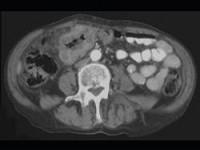

问题 男,45岁,右下腹胀痛、并可触及质硬包块,请结合图像选择最可能诊断()

选项 A.结肠Crohn病 B.结肠癌 C.肠结核 D.结肠淋巴瘤 E.慢性溃疡性结肠炎

答案 B